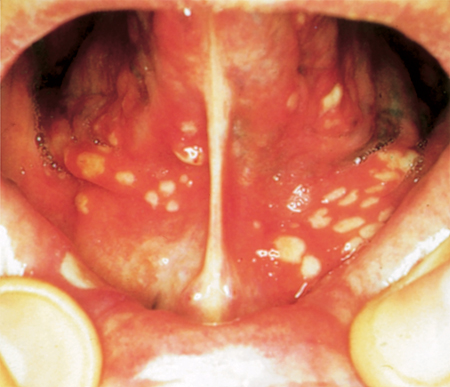

Major aphthae involve any oral site, including the keratinised mucosa (palate and dorsum of tongue). They are round or ovoid ulcers greater than 10 mm in diameter, and occur in groups of 1 to 6 at a time. They are often more painful and persistent than minor aphthae and heal slowly, over 10-40 days, or occasionally longer.[1][2][6][Figure caption and citation for the preceding image starts]: Recurrent aphthous stomatitis (RAS): major aphthaeFrom the personal collection of Crispian Scully, MD, PhD, FDSRCS, FRCPath [Citation ends].